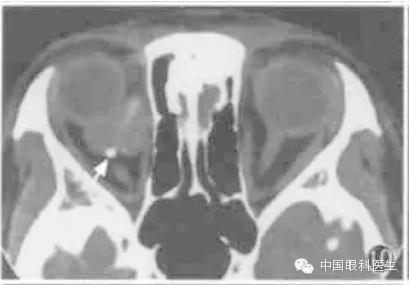

3.眼上静脉增粗

现代高分辨力CT可显示正常眼上静脉。眼上静脉起自内眦部,于视神经上方与上直肌间穿过眶中部,达眶上裂。临床上常见的眼上静脉增粗主要是颈动脉-海绵窦瘘。水平CT扫描显示视神经上方层面条索状高密度影,并自内侧斜向外侧(图14);冠状CT示视神经上方(或内上,外上)圆形高密度影。轻度增粗时需要与对侧比较。

图14 劲动脉海绵窦瘘CT显示右眼上静脉增粗,左侧为正常眼上静脉(箭头)